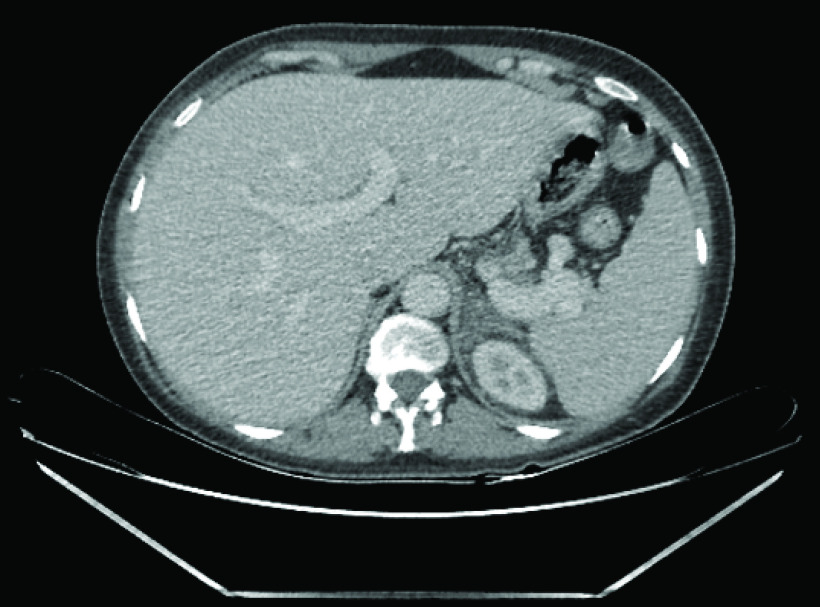

In postpartum period, the pain persisted and; therefore, surgical consultation recommended CT scan of the abdomen with contrast to rule out pancreatitis and splenic vein thrombosis. Subsequently the CT scan revealed left adrenal gland with decreased enhancement and adjacent inflammatory changes suggestive of an infarct. Right adrenal gland was normal. Normal appearing appendix, no anomalous vasculature was seen and MRI study was unlikely to add any more information; therefore, was not done.

Figure 1. . Computed tomography scan postpartum showing nonhemorragic adrenal infarction on the left side.

Figure 2. . Computed tomography scan showing the left kidney and the left infarcted edematous adrenal gland in the immediate postpartum period.